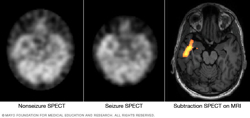

Pinpointing seizure location

These SPECT images show the blood flow in the brain when there's no seizure activity (left) and during a seizure (middle). The subtraction SPECT coregistered to MRI (right) helps pinpoint the area of seizure activity by overlapping the SPECT results with brain MRI results.

- Single-photon emission computerized tomography (SPECT). This procedure measures blood flow in the brain during a seizure. Typically, blood flow is higher in the part of the brain where seizures occur. You are admitted to the hospital to have this test.